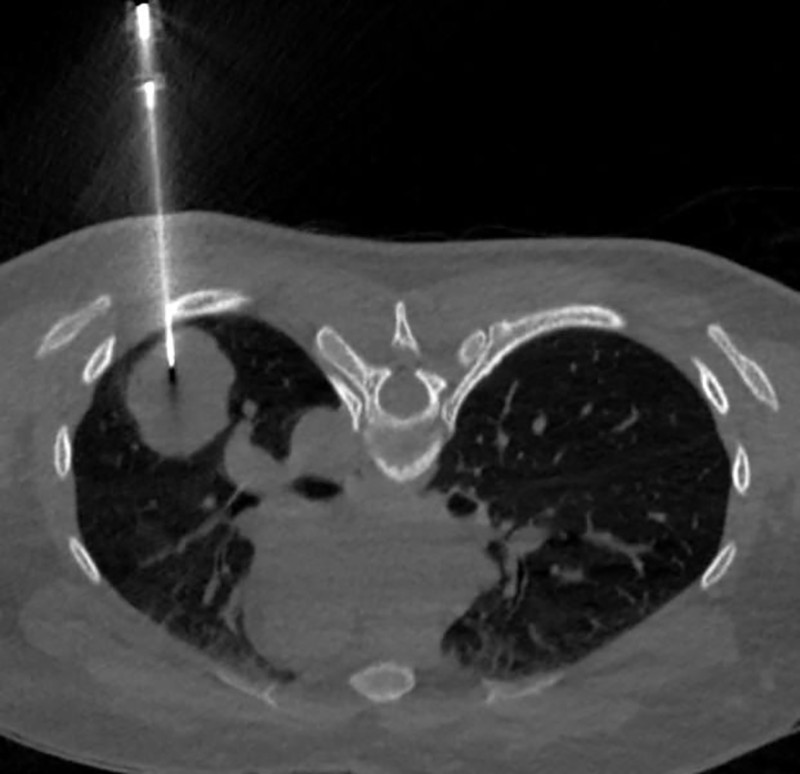

Chụp CT lồng ngực có tiêm cản quang phát hiện khối u thùy dưới phổi trái (LUNG-RADS 4B), kèm theo nốt nhỏ thùy giữa phổi phải, cần loại trừ tổn thương thứ phát.

Nhận định đây là ca bệnh phức tạp, không điển hình, PGS. Phượng đã chỉ định sinh thiết phổi dưới hướng dẫn CT để xác định bản chất tổn thương.

BSCKI. Trần Văn Thụ - Trưởng Khoa Chẩn đoán hình ảnh, Bệnh viện Đa khoa Medlatec là người trực tiếp thực hiện sinh thiết cho bệnh nhân.

Hình ảnh sinh thiết phổi dưới hướng dẫn CT/Ảnh Medlatec